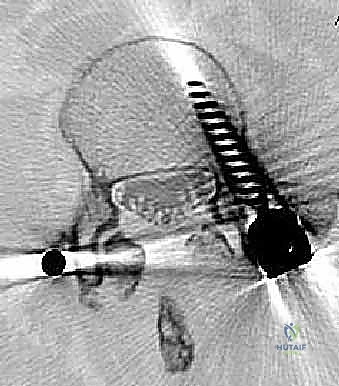

عملية دمج الفقرات (Spinal Fusion) هي إجراء جراحي يهدف إلى ربط فقرتين أو أكثر بشكل دائم، مما يزيل الحركة غير الطبيعية والمؤلمة بينهما، ويعيد الاستقرار الميكانيكي إلى العمود الفقري. في حالتنا هذه، يتم التركيز بشكل خاص على المنطقة الصدرية القطنية (Thoracolumbar Junction)، وهي المنطقة الانتقالية الحرجة التي تربط الجزء العلوي من الظهر (القفص الصدري الصلب) بالجزء السفلي (المنطقة القطنية المتحركة). يتم التثبيت باستخدام أدوات طبية معدنية متطورة (Instrumentation) مثل المسامير السويقية (Pedicle Screws) والقضبان المصنوعة من التيتانيوم.

السويقات الفقارية (Pedicles): دعامة التثبيت الأساسية والمحورية

تعتبر السويقة الفقارية (Pedicle) جسرًا عظميًا أسطوانيًا يربط الأجزاء الخلفية للفقرة (القوس الفقري) بالجسم الفقري الأمامي الضخم. في جراحة دمج الفقرات الحديثة، تعتبر السويقة نقطة التثبيت الرئيسية والأقوى للمسامير المستخدمة في العملية (Pedicle Screws). يختلف شكل وحجم وزاوية السويقات بشكل كبير على طول العمود الفقري، وفهم هذه الفروق الدقيقة أمر بالغ الأهمية للجراح لضمان وضع المسامير بأمان تام وفعالية قصوى دون الإضرار بالأعصاب أو الأوعية الدموية.

* التصوير المقطعي المحوسب (CT Scan): يوفر صوراً ثلاثية الأبعاد للعظام، وهو ضروري جداً للتخطيط الجراحي الدقيق وتحديد أحجام المسامير المناسبة لكل سويقة فقارية.